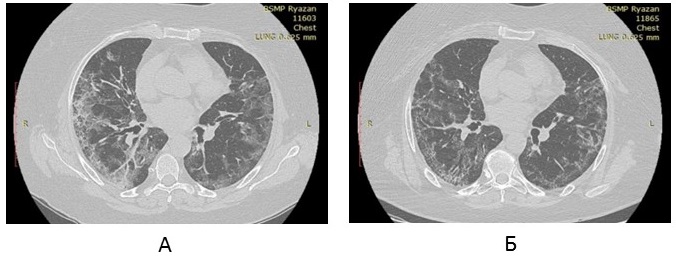

Repeated X-ray CT of lungs (18th day of illness, in hospital): in the central and peripheral areas of lungs on both sides, extended areas of consolidation of ground-glass opacity type of irregular shape with sharp slightly cord-like contours with emphaticalness of the intralobular interstitium in the lower lobes. The volume of involved lung parenchyma of the right lung — up to 40%, of the left lung — up to 35% (Figure 3A).

Fig. 3. Dynamics of changes of the results of X-ray computed tomography of lungs of patient R., 61 years old, with COVID-19, in the course of complex treatment including bovhyaluronidase azoximer: in the hospital on admission (18th day of illness, before start of therapy with bovhyaluronidase azoximer) (A), 27th day of illness (10th day of treatment with bovhyaluronidase azoximer) (B).

Therapy was given: dexamethasone intravenously, baricitinib, enoxaparin subcutaneously, bovhyaluronidase azoximer intramuscularly once every 3 days from the 18th day of the disease. In the course of therapy, the content of lymphocytes in peripheral blood was 1.0 x 109/l, CRP ― 10 mg/l, ferritin ― 320 µg/l, fibrinogen ― 365 mg%. Before treatment with bovhyaluronidase azoximer, SpO2 without oxygen insufflation was 90%, after the 2nd injection of SpO2 ― 93% without oxygen therapy.

X-ray CT of lungs in dynamics after 10 days (between two X-ray examinations, 3 injections of bovhyaluronidase azoximer were made as part of complex therapy): extended areas of consolidation of ground-glass opacity type of irregular shape with sharp slightly cord-like contours, evident intralobular interstitium in the lower lobes earlier observed in the central and peripheral areas of both lungs, restructured to smaller areas of cord-like consolidation and reticulation. The volume of the involved parenchyma of the right lung was up to 15%, of the left lung — to 10% (Figure 3B).

Thus, the dynamics of SpO2, X-ray CT changes of lungs in the course of complex therapy with bovhyaluronidase azoximer evidences not only the effect of the drug on the post-inflammatory pneumofibrosis, but also its potential ability to degrade hyaluronan that accumulates in the lung tissue in the earlier stages of the inflammatory process.